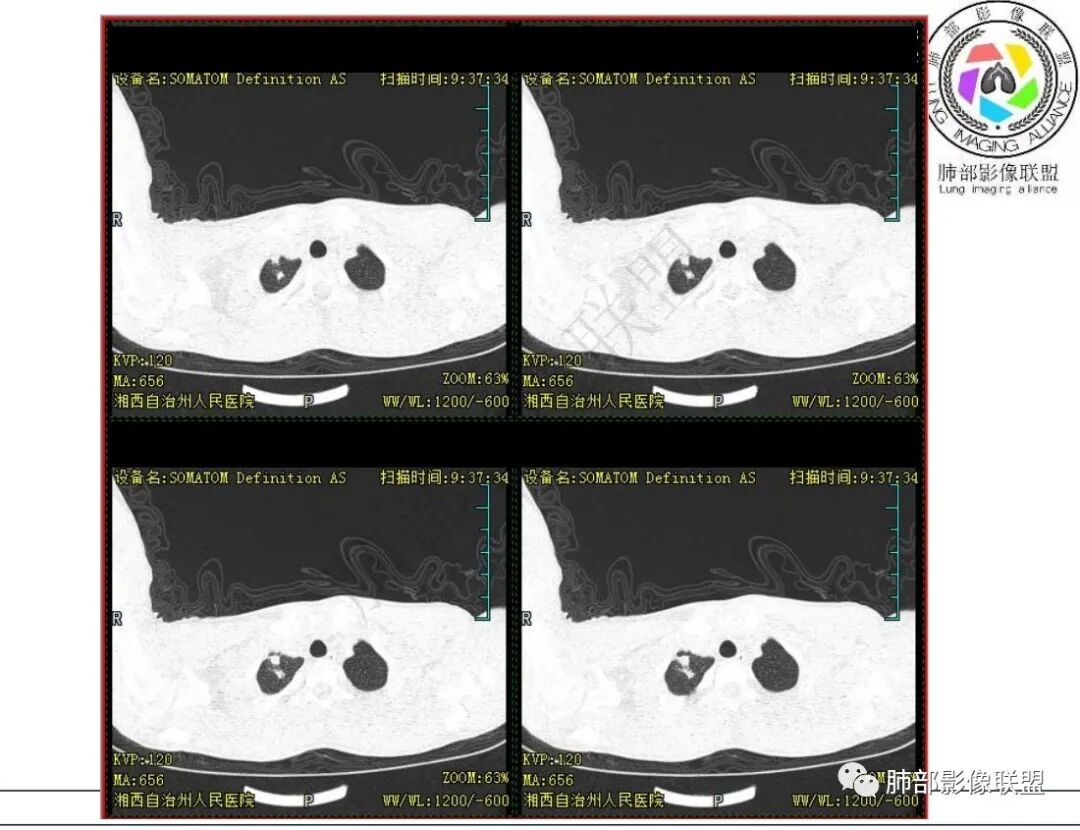

影像:右肺上叶多发实变影结节影,边界模糊,边缘收缩,伴多发空洞,洞壁光滑,部分支气管壁增厚。

3.首次CT提示:右肺上叶多发结节影及实变影,簇状分布,周围散在磨玻璃影,结节内多类圆形空洞,内壁光整,有一定张力,偶见液平。部分支气管壁增厚。

5.抛开分布不谈 其他的,临床中毒症状不明显、非易感人群,肺结节、实变、晕征、空洞等等都可以符合隐球感染。

本例病灶分布特点比较偏中央分布,不是我们常见的隐球外围胸膜下。看来诊断隐球,分布不能太绝对,至少不能作为绝对排除项。